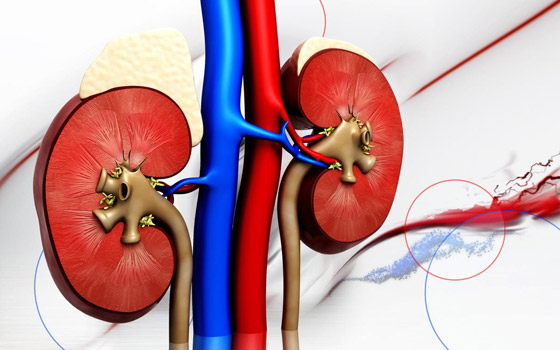

لمرضى الكلى.. هذه النصائح تحميكم من العدوى بفيروس كورونا

يؤثر مرض كورونا كوفيد-19 على الكلى والقلب والجهاز العصبي والدم والجهاز الهضمي. كما تشير الدراسات الحديثة إلى أن الأشخاص المصابين بأمراض الكلى أكثر عرضة للإصابة بعدوى فيروس كورونا المُستجد، بحسب ما نشره موقع أميركي. ووفقًا لصندوق الكلى الأميركي، إذا كان المريض يتلقى العلاج بالغسيل الكلوي ويعاني من مشاكل صحية أساسية، فربما يكون عرضة لخطر الإصابة بكوفيد-19.

تأثير كورونا على الكلى

أظهرت دراسة نُشرت في مجلة "كيدني إنترناشيونال" أن مرضى الكلى أكثر عرضة للإصابة بكوفيد-19 ويجب أن يلتزم مرضى غسيل الكلى ببروتوكولات صارمة لتقليل خطر الإصابة بالعدوى. وأشارت الدراسة إلى أنه من بين 536 مريضاً مصابين بالعدوى الفيروسية، أصيب 36 مريضاً بضعف حاد في الكلى خلال 20 يوماً من الإصابة بالفيروس على الرغم من وجود مستوى كرياتينين طبيعي في البلازما. وأثر الاختلال الكلوي الحاد على عوامل مختلفة أدت في النهاية إلى فشل متعدد الأعضاء، مما أودى بحياة 33 مريضاً يعانون من اختلال كلوي حاد.